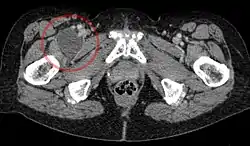

![]() Enlarged iliopectineal bursa in CT - scan | |

The iliopectineal bursa or the iliopsoas bursa is a large synovial bursa that separates the external surface of the hip joint capsule from the normally just the tendon of the iliopsoas muscle.[1]

The most proximal of part the iliopectineal bursa lies on the iliopubic eminence of the superior pubic ramus. The iliopectineal bursa passes across the front of the capsule of the hip joint and extends distally downwards almost as far as to the lesser trochanter.[2]

The iliopectineal bursa frequently communicates by a circular aperture with the cavity of the hip joint.[1]